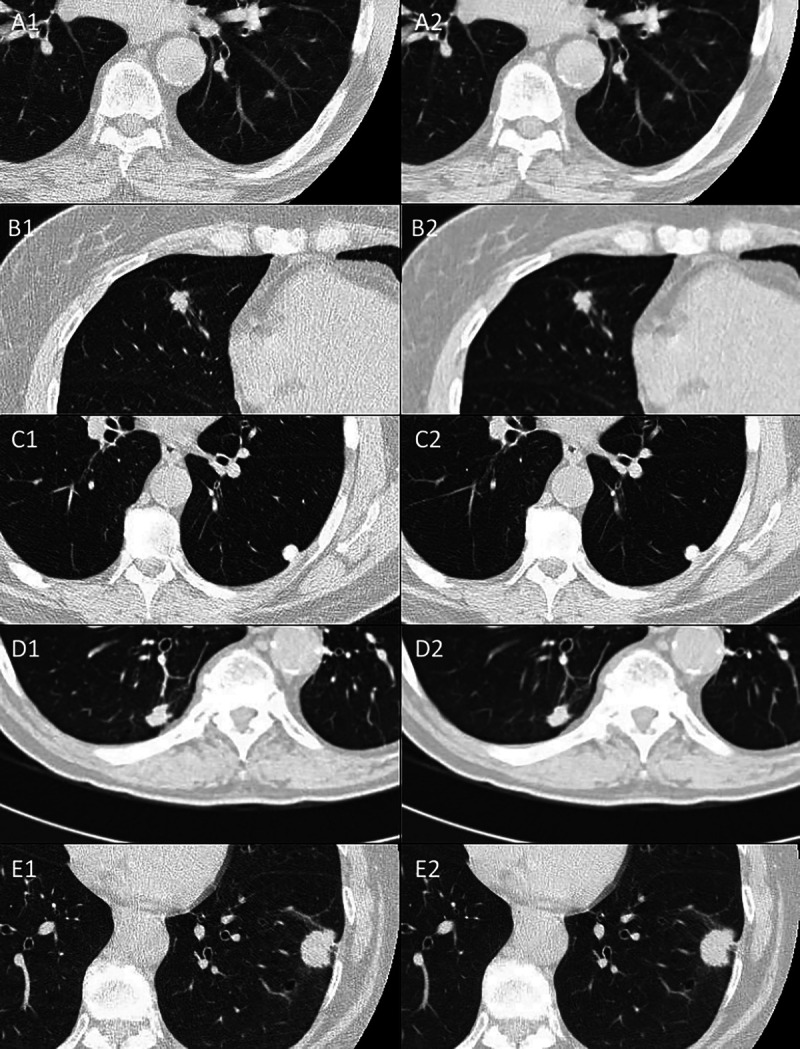

Abstract Image